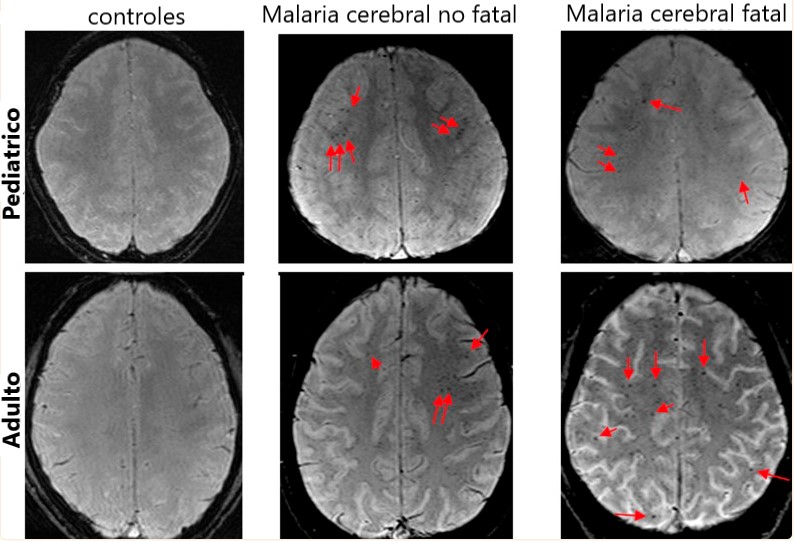

En lo que respecta a los eventos vasculares de la malaria, estos suelen afectar mayormente a la sustancia blanca del cerebro. Cuando ocurre, es común observar en los pacientes una disminución de la velocidad de procesamiento, un riesgo elevado de desarrollar alzhéimer, demencia y afasia. Así como síntomas de dislexia, apraxia y disfasia.

Las manifestaciones clínicas que puede observarse en niños y adultos son diferentes, manifestando claros ejemplos neurológicos y neuropsicológicos. Aspectos que se reportan predominantemente por las complicaciones vasculares y neurotóxicas.

Particularmente en los niños, la malaria puede reflejarse en forma de crisis tónico-clónicas en todo el cuerpo presentando, en ocasiones, crisis similares a la epilepsia. De igual modo, los menores presentan alteraciones de consciencia, con déficits en áreas prefrontales con dominio de juicio, aunque tales alteraciones pueden variar en cada caso.

En suma, recientemente se ha corroborado que en niños las secuelas de malaria son graves pese al tratamiento. Esto se debe a las toxinas que, esparcidas en el torrente sanguíneo, generan considerables daños cognitivos, sobre todo en la velocidad de procesamiento e información, causando déficits en adquisición y reproducción de lenguaje (Albrecht-Schgoer et al., 2022).